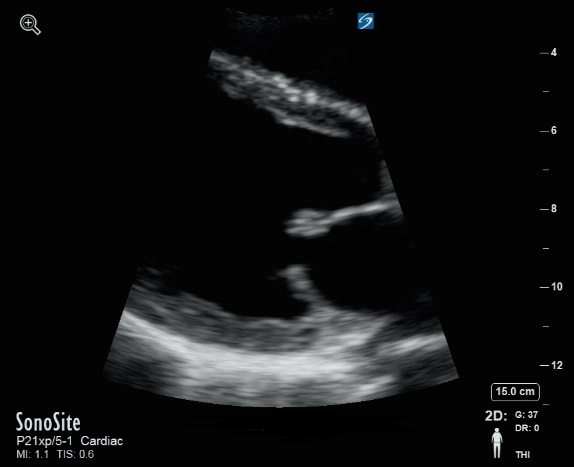

Vergrößerte Mitralklappen